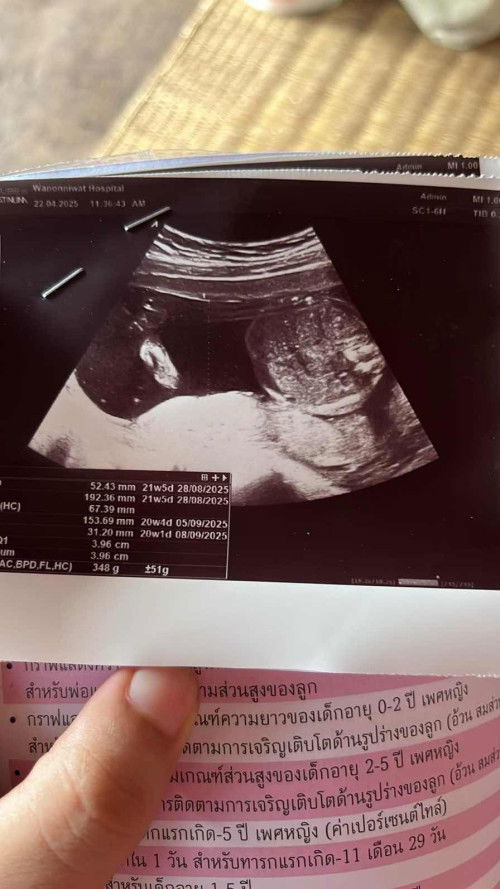

แบบนี้ดูยังไงคะ น้องอยู่ท่าไหน#ท้องแรก #ช่วยบอกกันหน่อยนะคะ #แม่มือใหม่